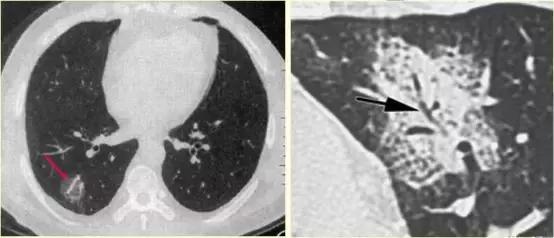

柱状支气管扩张(可逆问题)——“轨道征”

慢性支气管炎继发柱状支气管扩张——“轨道征”

柱状支气管扩张与扫描层面垂直——“印戒征”

附:支气管粘液嵌塞

粘液支气管征或支气管粘液嵌塞:是由于扩张的支气管腔内分泌粘液无法排出或近端梗阻而郁积等原因所致。

CT表现:表现为分支状或指状致密影,呈指套征或“V”、 “Y”形征。

意义:表明有支气管扩张分泌粘液,支气管近端有梗阻粘液不能排出而郁积以及支气管闭索等。

意义:支气管扩张粘液分泌郁积,支气管近端梗阻等

分析考虑:扩张的支气管充满粘液呈纵行束状排列